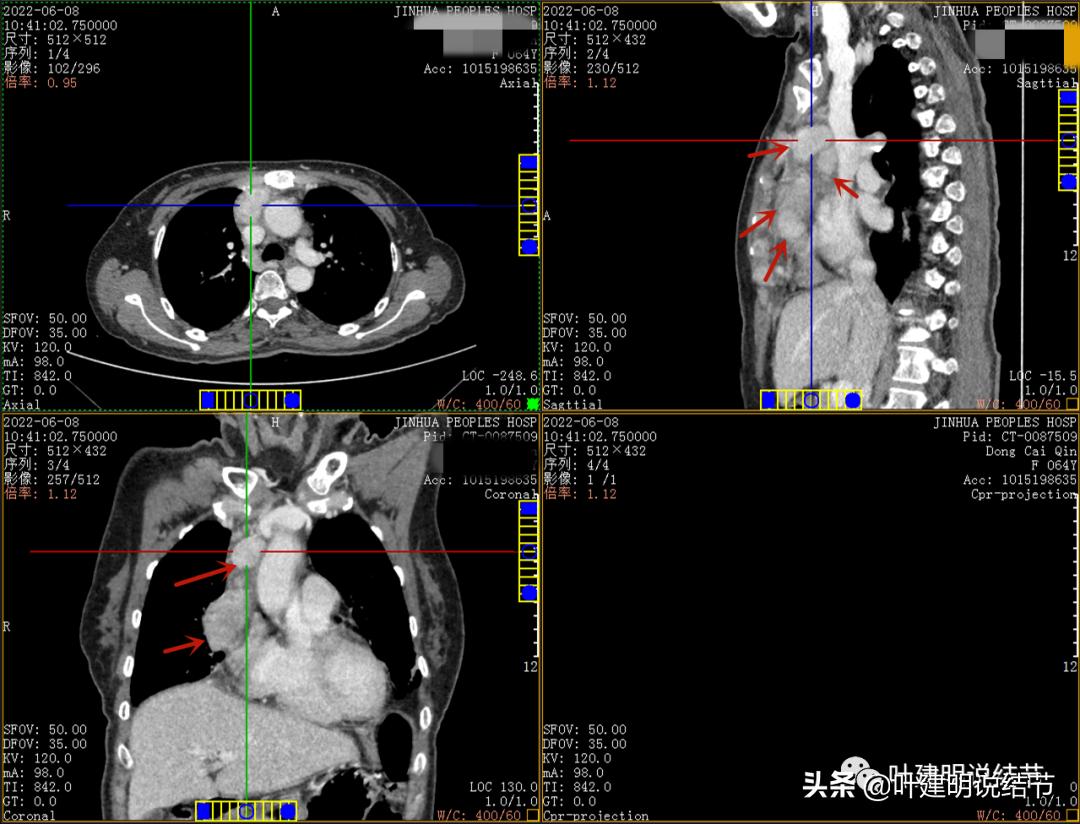

近膈面病灶的轴位、冠状位与矢状位所见

病灶占据前纵隔从上到下全程,多中心,密度不均,对心脏与大血管有压迫,没有明显侵犯

病灶表面不平,中间有坏死

特别显示与无名静脉的关系

上图示最大横断位达5厘米